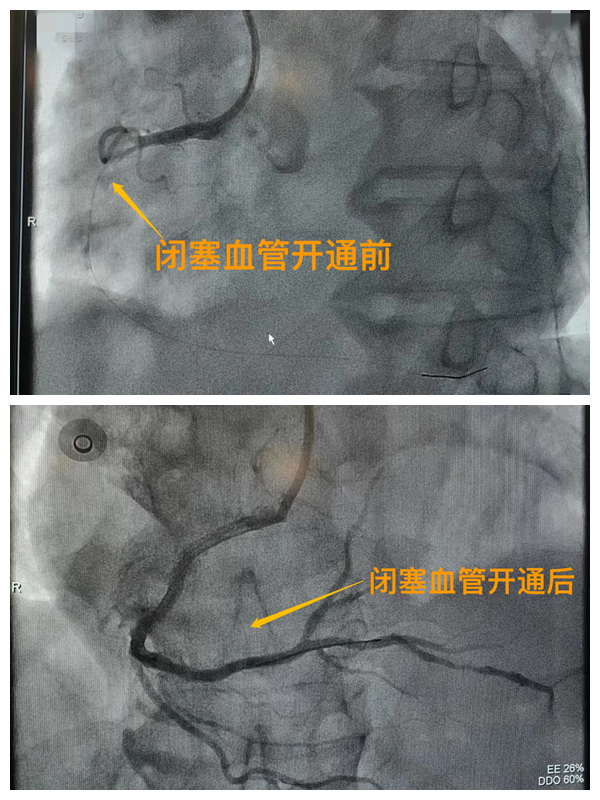

市二院胸痛中心于2021年12月23日通過中國胸痛中心認證,成為國家級胸痛中心,先后開展了冠心病的介入診療、心律失常的心內電生理檢查及射頻消融治療、永久起搏器植入、先天性心臟病的介入封堵及臨時起搏器植入、主動脈內球囊反搏治療等,完成心臟介入手術3000余例。多次創造從入院至行急診介入手術開通血管(入門-導絲通過)30分鐘以內記錄,極大保證了患者的生命安全,提高了預后質量,挽救了眾多急性心梗患者的生命。(尹紅婭       張   靜)